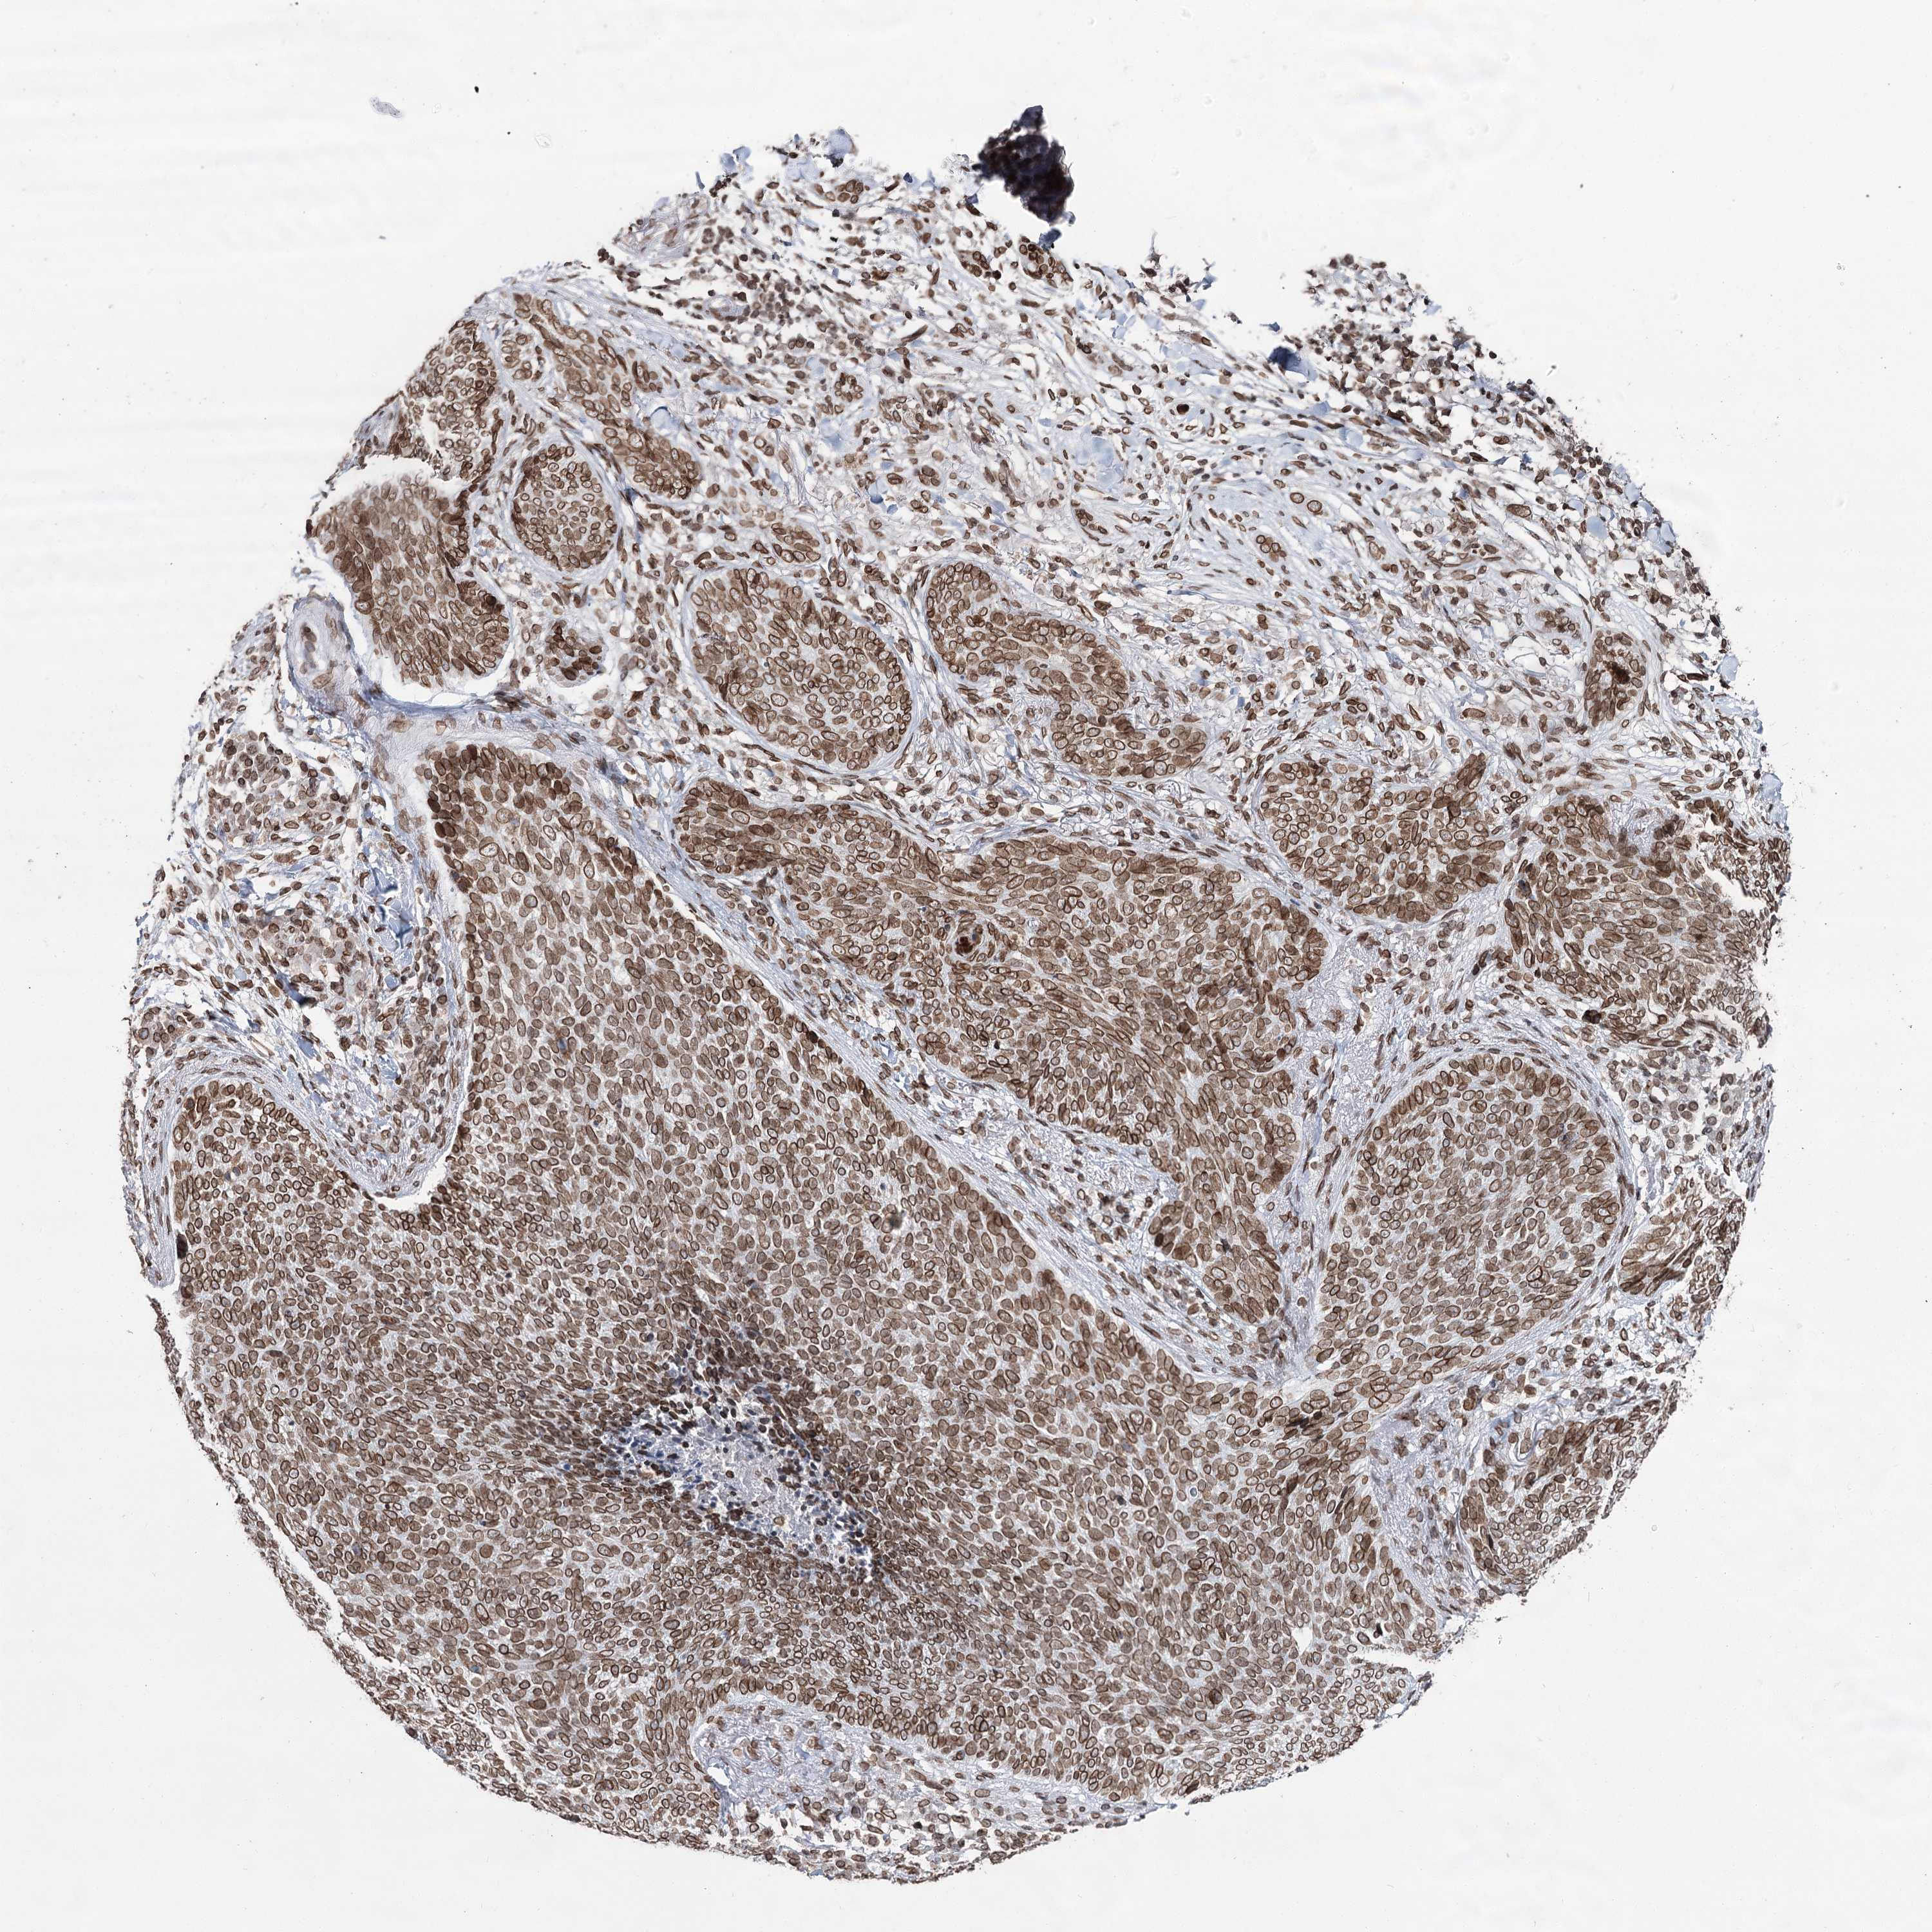

SKIN CANCER - Protein expressioni

A mouse-over function shows sample information and annotation data. Click on an image to view it in a full screen mode. Samples can be filtered based on level of antibody staining by selecting one or several of the following categories: high, medium, low and not detected. The assay and annotation is described here.

Antibody stainingi

Antibody staining in the annotated cell types in the current human tissue is reported as not detected, low, medium, or high, based on conventional immunohistochemistry profiling in selected tissues. This score is based on the combination of the staining intensity and fraction of stained cells.

Each image is clickable and will lead to virtual microscopy that enables deeper exploration of all samples and also displays staining intensity scores, fraction scores and subcellular localization as well as patient and tissue information for each sample.

Antibody HPA038091

Staining

High

Intensity

Strong

Quantity

>75%

Location

Nuclear

Squamous cell carcinoma, NOS

Squamous cell carcinoma, metastatic, NOS